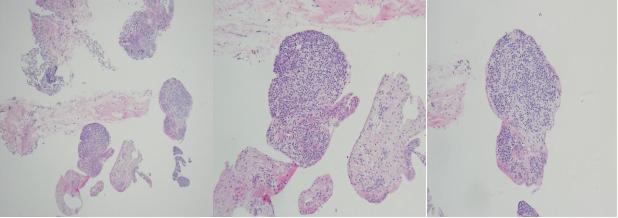

肺组织病理:

顾莹莹 教授解读:

右下肺基底段的活检,见大量淋巴细胞浸润,夹杂浆细胞,但未见明确中性粒细胞,考虑慢性炎症性细胞浸润,可见多个边界清楚的肉芽肿性病灶及多核巨细胞,小血管上未见明确血管炎改变,肉芽肿病灶未见坏死表现,以类上皮细胞为主,散在多核巨细胞,周围未见纤维组织包裹,要考虑鉴别感染与非感染性肉芽肿。该患者背景可见炎症细胞浸润,首先考虑感染,但抗酸及六胺银染色均为阴性。隐球菌可导致肉芽肿性改变,但往往比较散在,以多核巨细胞为主,多核巨细胞内常可见吞噬隐球菌孢子,该患者肉芽肿比较紧密。结节病不会出现坏死,周围可见纤维母细胞包裹,背景淋巴细胞不多,亦不会出现咯血症状,大多数患者为体检发现,影像学可见纵隔及双肺淋巴结改变,该患者不符合。患者肺泡腔未见机化,肺组织未见肿瘤及血管炎改变,整体看考虑感染可能性大,重点排查分枝杆菌,增值性结核可见肉芽肿性改变,但往往可见朗格汉斯细胞,该患者以多核巨细胞为主,考虑非结核分枝杆菌感染可能性大。